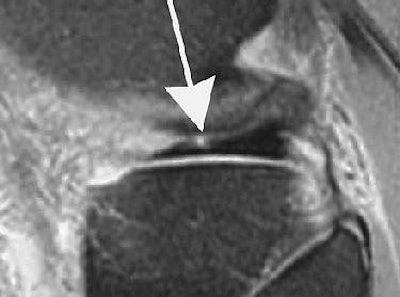

![]() |

| Marching cleft sign in discoid lateral meniscus indicates radial meniscal tear in 21-year-old man. Conventional sagittal proton density image (TR/TE, 2,000/20) with fat saturation shows partial cleft (arrow) in most peripheral body segment. |